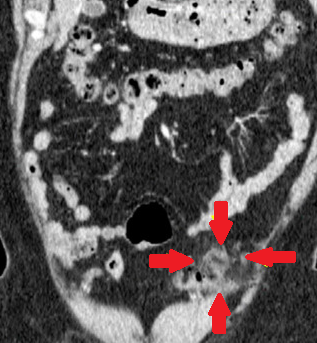

Σχήμα 1 . Η αξονική τομογραφία με ενισχυμένη με σκιαγραφικό έδειξε μια ακανόνιστη περιφερική μάζα στο αριστερό μισό του εγκάρσιου κόλου με λιπώδη συσσωμάτωση δίπλα σε παχυσμένο τοίχωμα του εντέρου. ( Ευγενική παραχώρηση Δρ. Β. Πενόπουλος ) .